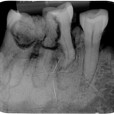

Tanden op kaakdeel (Rechts)   M3 derde kies (verstandskies ontbreekt )  M2 tweede grote kies. M1 eerste grote kies..

P2 tweede kleine kies .P1 eerste kleine kies . een hoektand , twee snijtanden .

Tanden op kaakdeel (Links)     M3 derde kies (verstandskies ontbreekt )  M2 tweede grote kies half gebroken . M1 eerste grote kies.half gebroken

.P2 tweede kleine kies .P1 eerste kleine kies ontbreekt  , een hoektand , twee snijtanden .